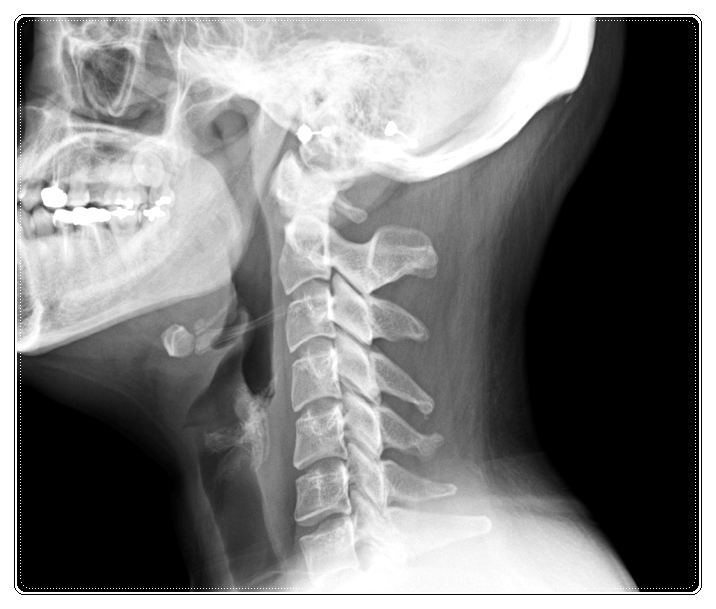

Q. 두개골과 경추까지 함께 봐야 하는 이유

많은 분들이 ‘턱만 치료하면 나아지지 않을까?’라고 생각하시는데요.

물론 경우에 따라 턱관절만 관리해도 불편함이 줄어드는 분들도 있습니다.

하지만 두개골과 경추는 하나의 무게중심을 공유하고 있어서

한쪽이 기울면 다른 쪽이 계속 부담을 받습니다.

턱과 목도 마찬가지로 두 축을 함께 맞춰야

증상이 완화되고, 다른 손상을 예방하는 데 도움이 됩니다.